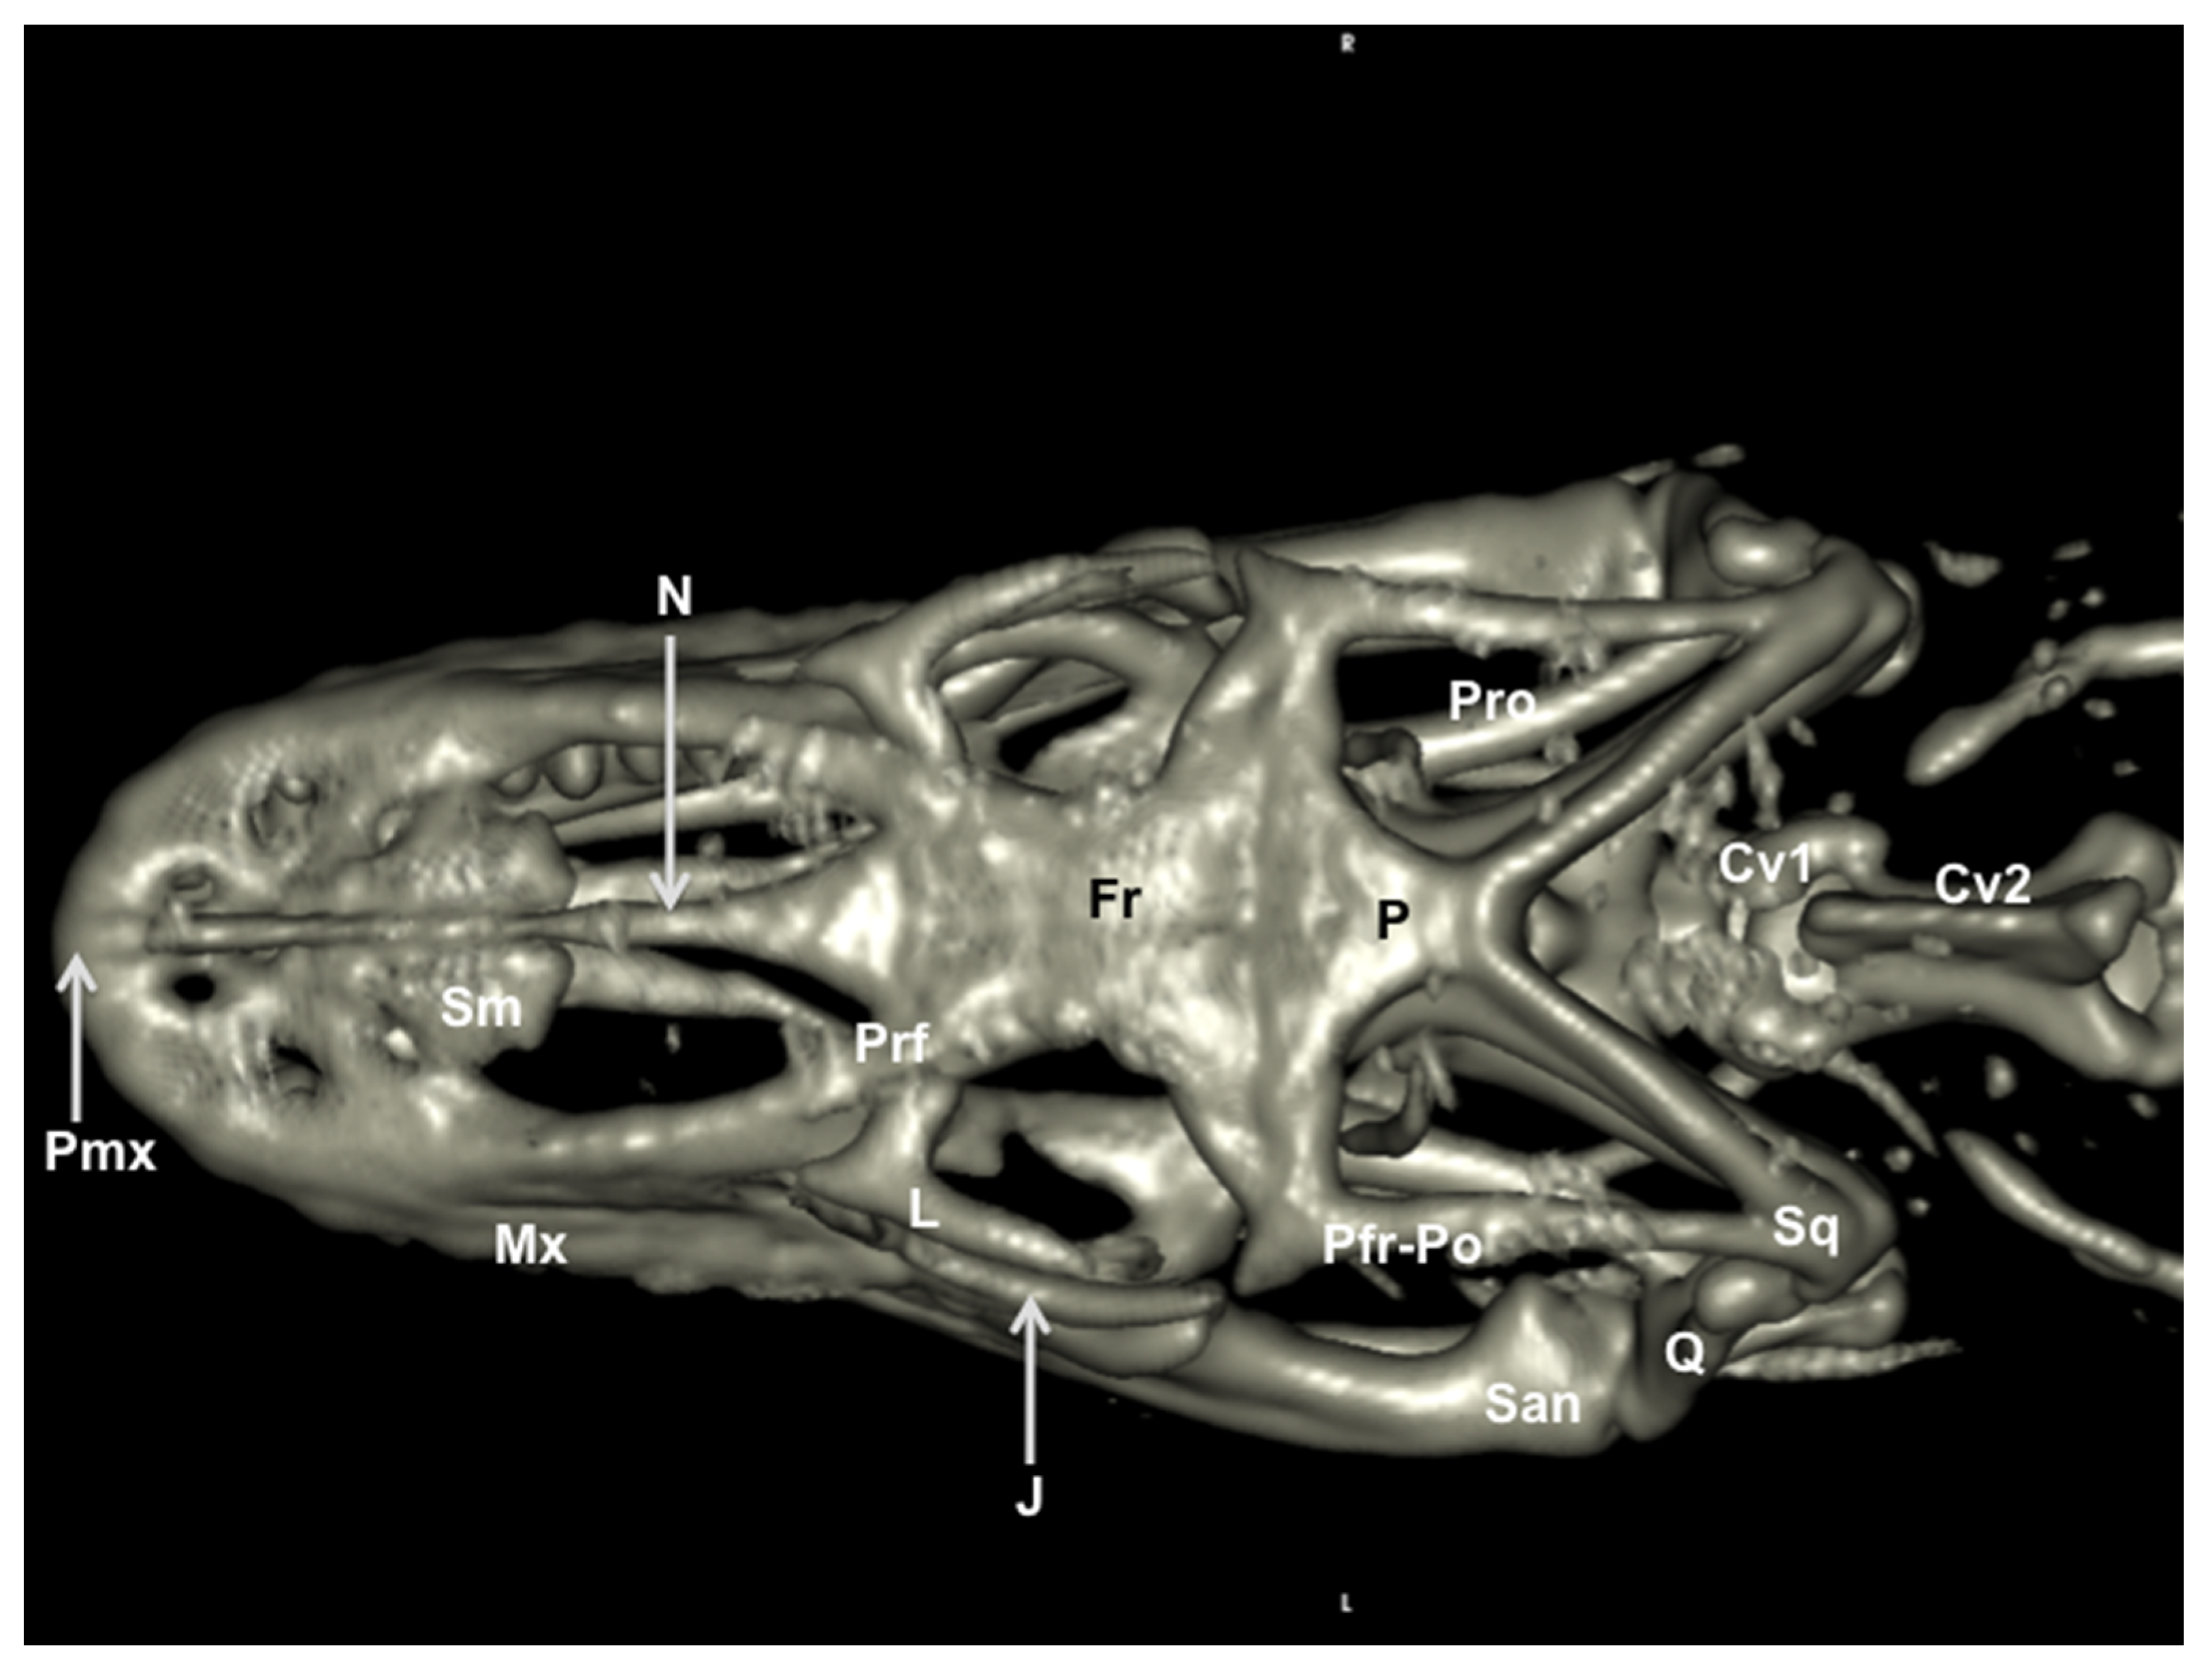

3.2. Head Volume-Rendered Reconstructed Images